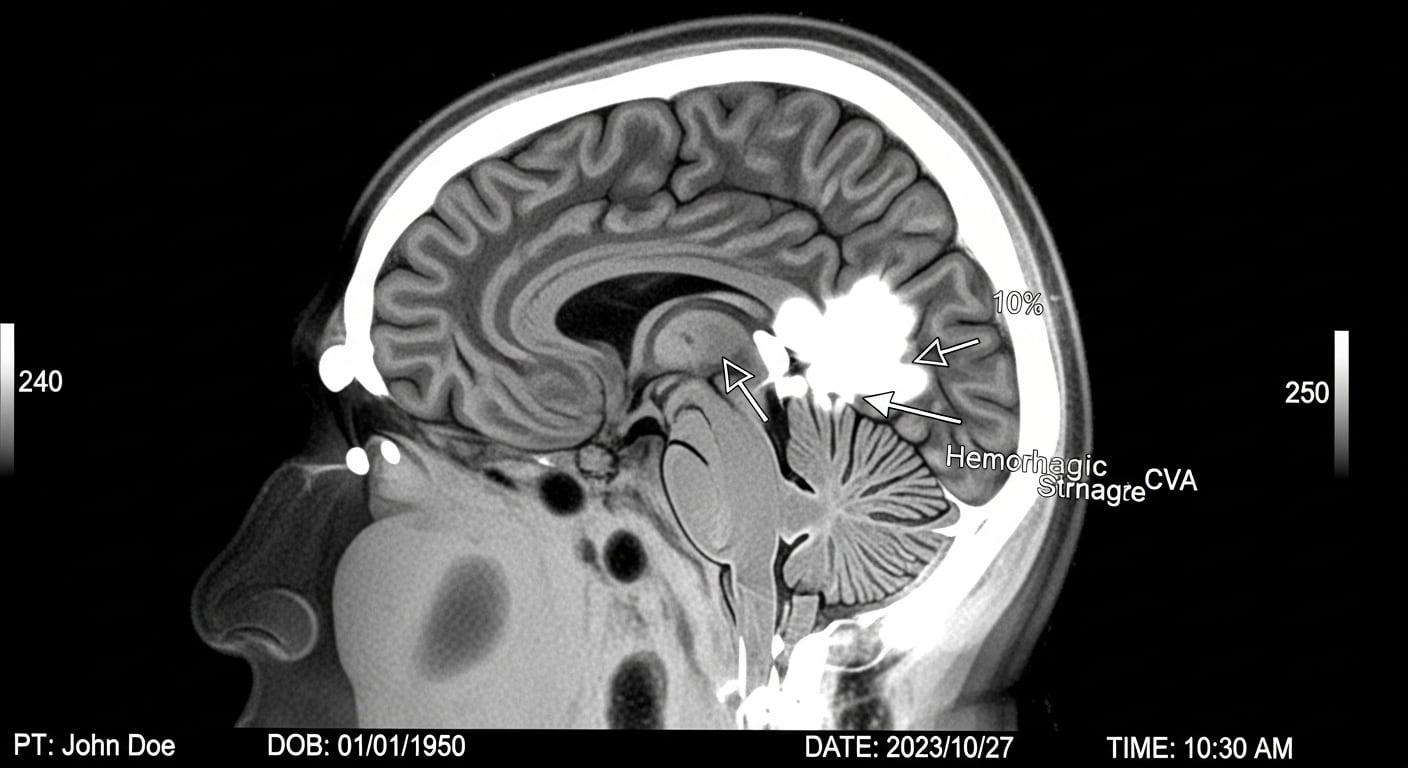

El nuevo escáner destaca porque capta señales más pequeñas, ve mejor las estructuras profundas y muestra cómo trabajan distintas partes del cerebro. Además, puede distinguir entre problemas diferentes, como tumores o daños por enfermedades como el Alzheimer y el Parkinson.

Según Carson, la capacidad de ver detalles tan pequeños y seguir la evolución de la enfermedad en menos tiempo mejora el diagnóstico y el control de los tratamientos. También permite ver si un tumor responde al tratamiento o si lo que se observa es una inflamación causada por la terapia, algo difícil de distinguir hasta ahora.

El NeuroEXPLORER también ayuda a los científicos a estudiar mejor cómo funcionan las conexiones entre las neuronas y cómo se envían las señales en el cerebro. Esto es clave para investigar enfermedades como el Alzheimer, porque permite ver problemas muy pequeños en los primeros momentos y hacer controles en el tiempo para ver cómo avanza la enfermedad.